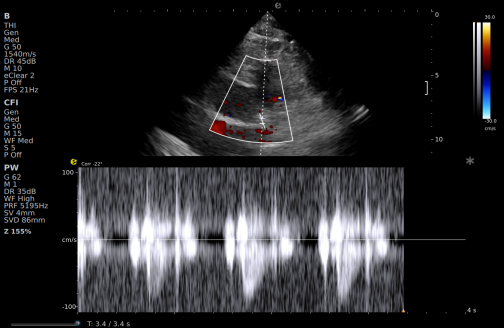

一例胸闷患者,临床采用无创冠脉超声作为初步评估手段,检查中发现:

彩色多普勒:敏感捕捉到局部血流加速现象;频谱多普勒:测得峰值血流速度明显升高,频谱形态异常。

彩色多普勒

频谱多普勒

基于超声提示的异常发现,临床为患者安排了冠脉CTA检查,结果显示前降支近段存在约45%狭窄,与超声提示的血流动力学改变高度一致。

这一病例体现了冠脉超声作为初筛工具的重要价值:它能够无创、实时地评估冠脉血流动力学状态,为后续是否需要进一步影像检查提供重要参考。超声与CTA的协同应用,既能评估结构变化,又能反映功能状态,为临床诊断提供了更全面的信息。